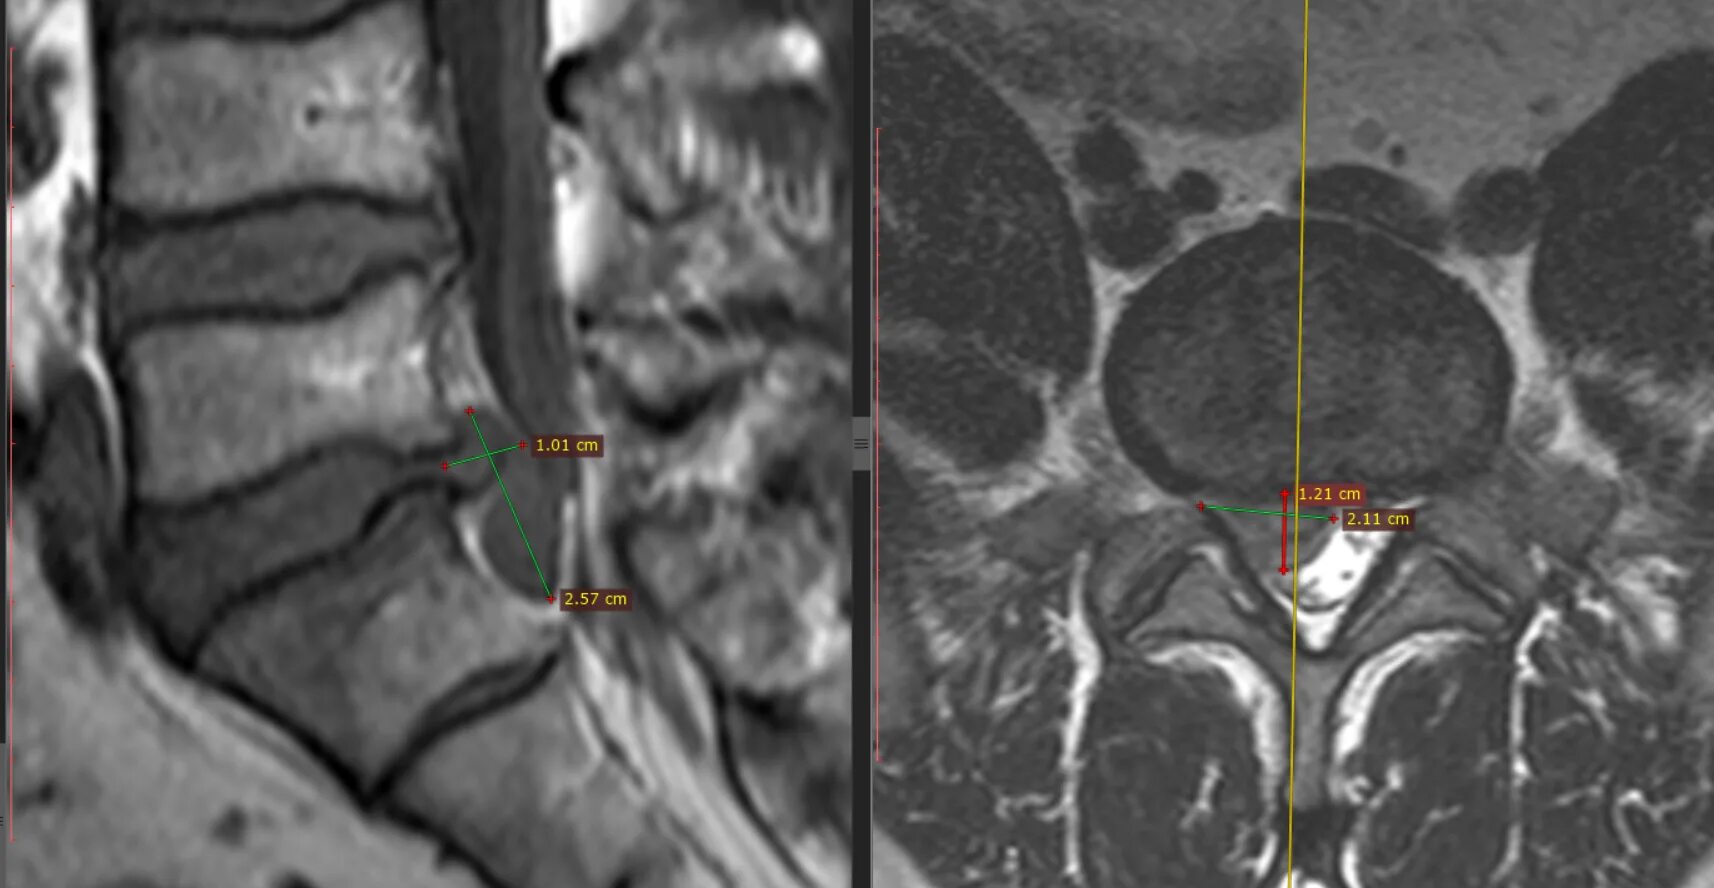

Грыжа диска с6 с7